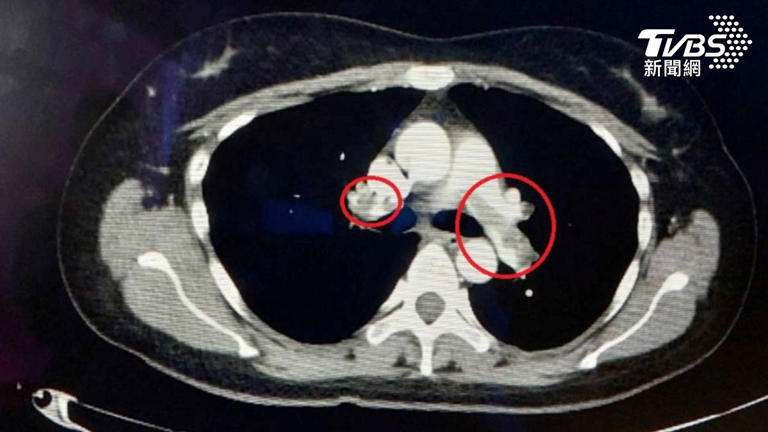

肺動脈栓塞依狀況不同而有不同的治療方式。(圖/TVBS) 苗栗一名76歲的黃姓老翁,因長期氣喘及走路很喘就醫,檢查發現雙側的肺動脈竟有大量的血栓,必須立刻接受治療;另一位32歲的劉小姐則因躺在床上會喘,且呼吸變得困難而到急診就醫,同樣在肺動脈發現血栓,導致肺栓塞。大千綜合醫院心臟外科主任李俊毅提醒,肺動脈栓塞是一種威脅生命的急性疾病,造成的影響從咳嗽、呼吸喘到猝死都有可能發生。 32歲的病人因長期躺臥,導致肺栓塞。(圖/TVBS) 肺動脈栓塞是血栓阻塞肺動脈或其分支,造成肺循環血流受阻,進而導致呼吸及循環功能障礙。依照阻塞的位置、血塊大小以及血流受阻的範圍,會發生不同的症狀,包含:突發性呼吸困難、胸痛、咳嗽、咳血、心悸、昏厥、低血壓、休克、下肢疼痛腫脹等。輕症或無症狀的病人多數很難及時被發現,而嚴重型的病人則可能快速發展為休克、甚至死亡,因此肺動脈栓塞又被稱為「沉默的殺手」,即使在健康的人身上也可能會突然發生。 李俊毅醫師。(圖/TVBS) 李俊毅主任表示,肺動脈栓塞多數是因下肢深部靜脈血栓脫落,順著血流通過右邊的心臟,再進入肺循環而形成。因此常見的危險因子包括:長時間不動,像是長途飛行、住院臥床、手術,尤其是骨科、腫瘤外科、婦產科手術、惡性腫瘤、肥胖、抽菸、口服避孕藥或荷爾蒙治療、有靜脈栓塞病史、懷孕及產後、高齡、遺傳性血栓傾向等。 黃姓老翁因為屬於慢性血栓,無法以藥物治療,所以採用自費微創智慧血栓清除系統,以抽吸的方式直接移除陳舊已久的血塊。病人治療前血氧已降到80%,遠低於正常人的95-100%,當雙側血栓移除完成時,病人血氧立即恢復正常,走路距離長也不覺得喘。 另一位32歲的女病人,是因小腿骨折手術後行動不便,就長時間躺臥在沙發上,先是手術的腳發生腫痛,然後就開始出現呼吸喘的症狀。由於血栓形成的時間小於2週,加上骨科手術部位穩定,因此先放置下腔靜脈濾網,避免下肢靜脈血栓再跑到肺部,再使用自費超音波震盪溶栓導管搭配血栓溶解藥物治療。病人2天後移除導管,透過肺動脈造影檢查,確認血栓已完全溶解,肺部血流流動正常,並於隔天出院返家。 李俊毅主任提醒,多數的肺動脈栓塞是可以預防的,像是手術前及住院期間可與醫師討論是否需要使用抗凝藥物預防靜脈血栓、手術後應早點下床活動避免長期臥床、穿著壓力襪或使用間歇性氣壓裝置促進下肢血流回流、調整生活習慣、戒菸、控制體重及慢性疾病等,都能幫助民眾遠離肺動脈栓塞的威脅。 |